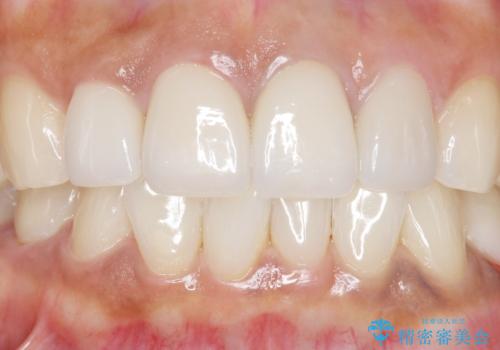

5年前のクラウン装着時と比較したところ、歯肉が成熟し歯間乳頭ができており、より天然歯のように自然に見えました。

患者様の良好なセルフケアと精密な適合の良いクラウンにより、歯肉の腫脹や退縮も認められませんでした。